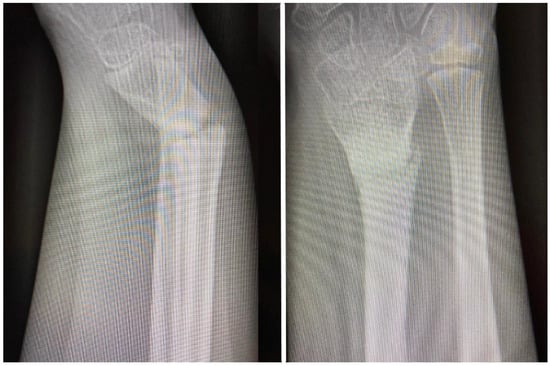

Post-operatively, the patient was immobilized in a cast splint for dressing protection, with gravitational drainage with the forearm in a sling, and presented for follow-up at two and four weeks. At 6 weeks, he was admitted for K-wire removal. However, after the removal of the K-wires the forearm became painful over the next few days, with progressive deformity of the distal forearm, which sent the patient back to the hospital in one week, and a radiological control exam was obtained. The fracture appeared with slight callus formation and volar angulation of the radius fracture. Because of the radiological aspect suggesting callus formation, the patient underwent soft orthopedic manipulation with reduction and was placed in a splint for four weeks. At the end of the 4-week immobilization, the splint was removed and a radiological exam obtained (Figure 3). At this point, 10 degrees of volar angulation was considered acceptable and the patient was advised to mobilize the hand and wrist as tolerated. Bear in mind that here we were situated in week 11 in this case’s chronology. Recovery did not develop as expected as there was intermittent pain with movement, a lack of mobility progress and progressive recurrence of the distal forearm deformity.

Follow-up exams were scheduled monthly, but the patient did not present until 6 months post-operatively, with pain over the forearm, increased pain with movement of the radiocarpal joint and thumb, moderate loss of range of motion and objective deformity of the distal forearm with no history of recent trauma. A plain radiograph was obtained (Figure 4).

Figure 3. AP and lateral views obtained at the end of four weeks’ immobilization, demonstrating 10 degrees of volar angulation, which was considered acceptable at this point, but with inadequate callus formation.

Figure 4. AP and lateral views obtained at 6 months after rehabilitation failure and recurrent pain with movement, demonstrating a lack of union and gross angulation of the radius and good healing of the ulna.